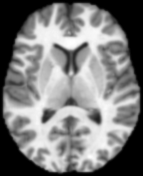

5 Application to Brain MR Images

An important building block for the analysis of brain MRI populations is the definition of a metric that measures how different two brain MRI are. A mathematically well motivated and popular approach for distance computations between brain images is based on large deformation diffeomorphic metric mappings (LDDMM (Miller et al., 2002)). Here we explore optimal transport distance as an alternative metric for comparing brain images.

To solve for the optimal transport map between two 3D brain images we extract for each image a point cloud from the intensity volumes. Each point represents a voxel as a point in 3-dimensional space, the location of the voxel. The mass of the point is equal to the intensity value of the voxel, normalized to sum to one over all points. For illustration, Figure 9 shows a single slice extracted from the original volumes and optimal transport maps between the two slices. This 2D problem resulted in point set of approximately points.

|

|

| (a) | (b) |

|

|

| (c) | (d) |